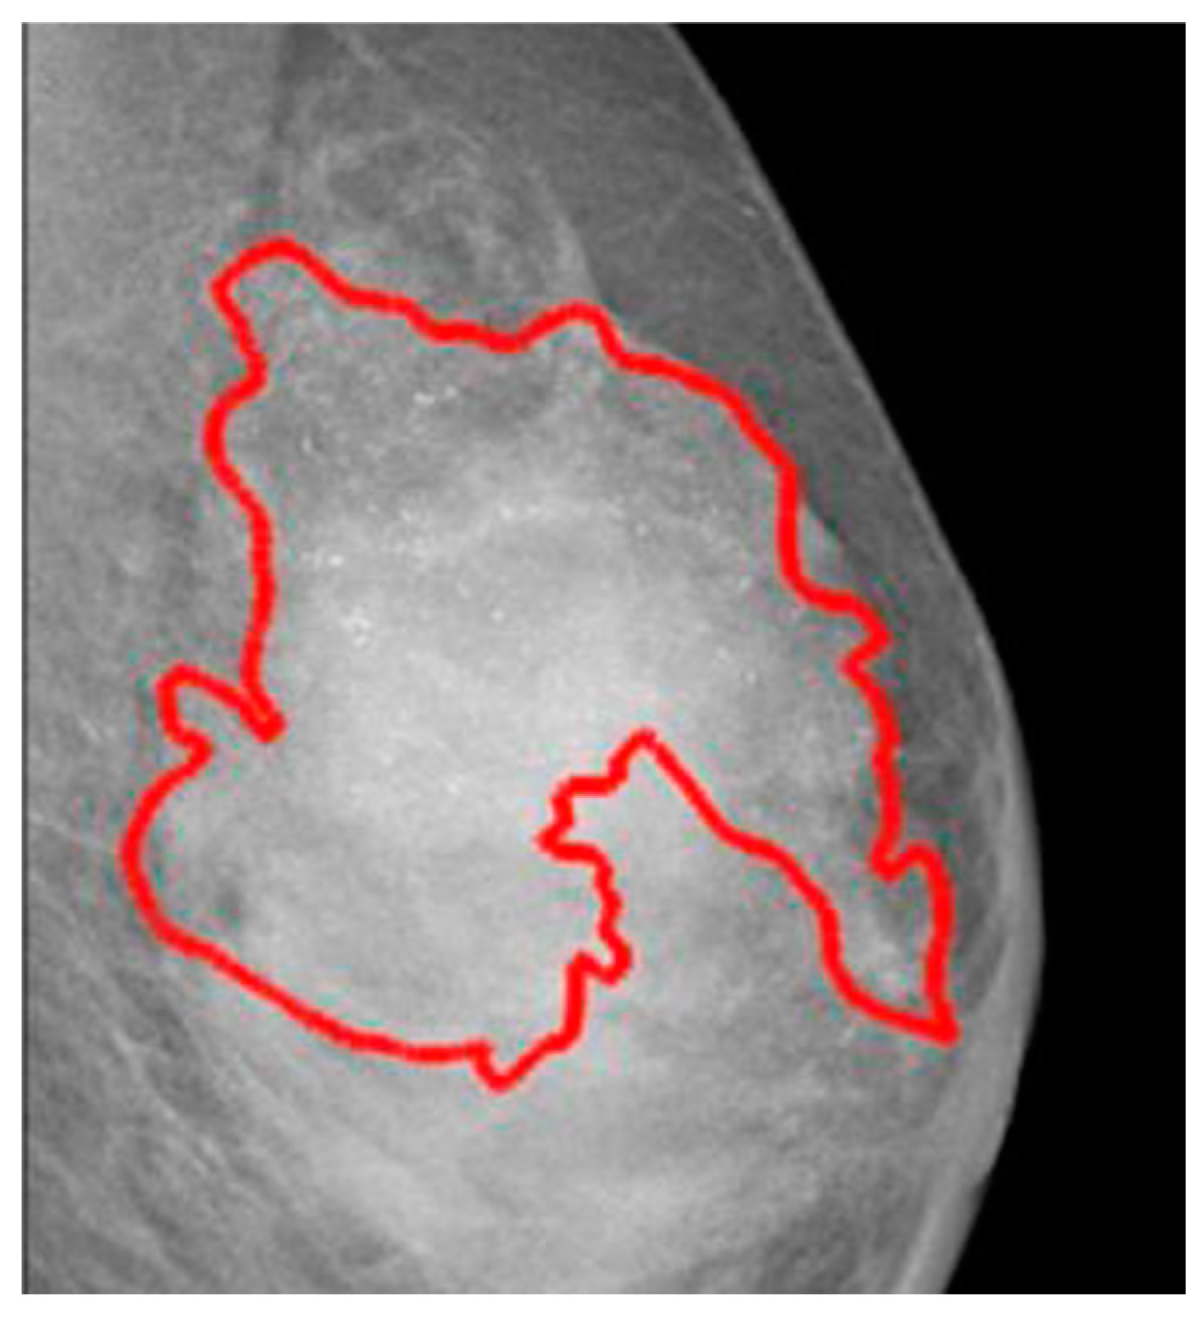

4.2.1. CBIS-DDSM

The CBIS-DDSM database features comprehensive annotations ideal for various classification, detection, and segmentation tasks. Lesion annotations are provided as binary masks (Figure 2) that accurately outline the regions of interest (ROI) surrounding the findings, which are classified into masses or calcifications. These masks are stored in DICOM format, identical to the original mammograms. Furthermore, the dataset includes classification labels validated by histopathology, indicating whether the findings are benign or malignant. A key benefit of this database is the inclusion of the BI-RADS assessment score within the annotations [23].

The CSAW-CC database offers various subsets suitable for cancer classification, detection, or segmentation in mammograms. However, not all samples feature detailed annotations with exact region of interest (ROI) contours, as presented in Figure 3. The pixel-level annotations encompass tumors identified at diagnosis, those noted during prior screenings, and areas where no tumors were present during earlier evaluations. These annotations provide measurements of tumor area (in square pixels) and the length of the major axis (in pixels) for both diagnosis and prior screenings. Tumors are categorized as invasive, in situ, or a combination of both. A limitation of the CSAW-CC database is the lack of specific BI-RADS scores. Similarly to the OMI-DB database, CSAW-CC’s primary advantage is its regular screenings, which might help to track tumor progression by using past annotations that show where tumors were located. Additionally, the database emphasizes real-world variability in age [19].